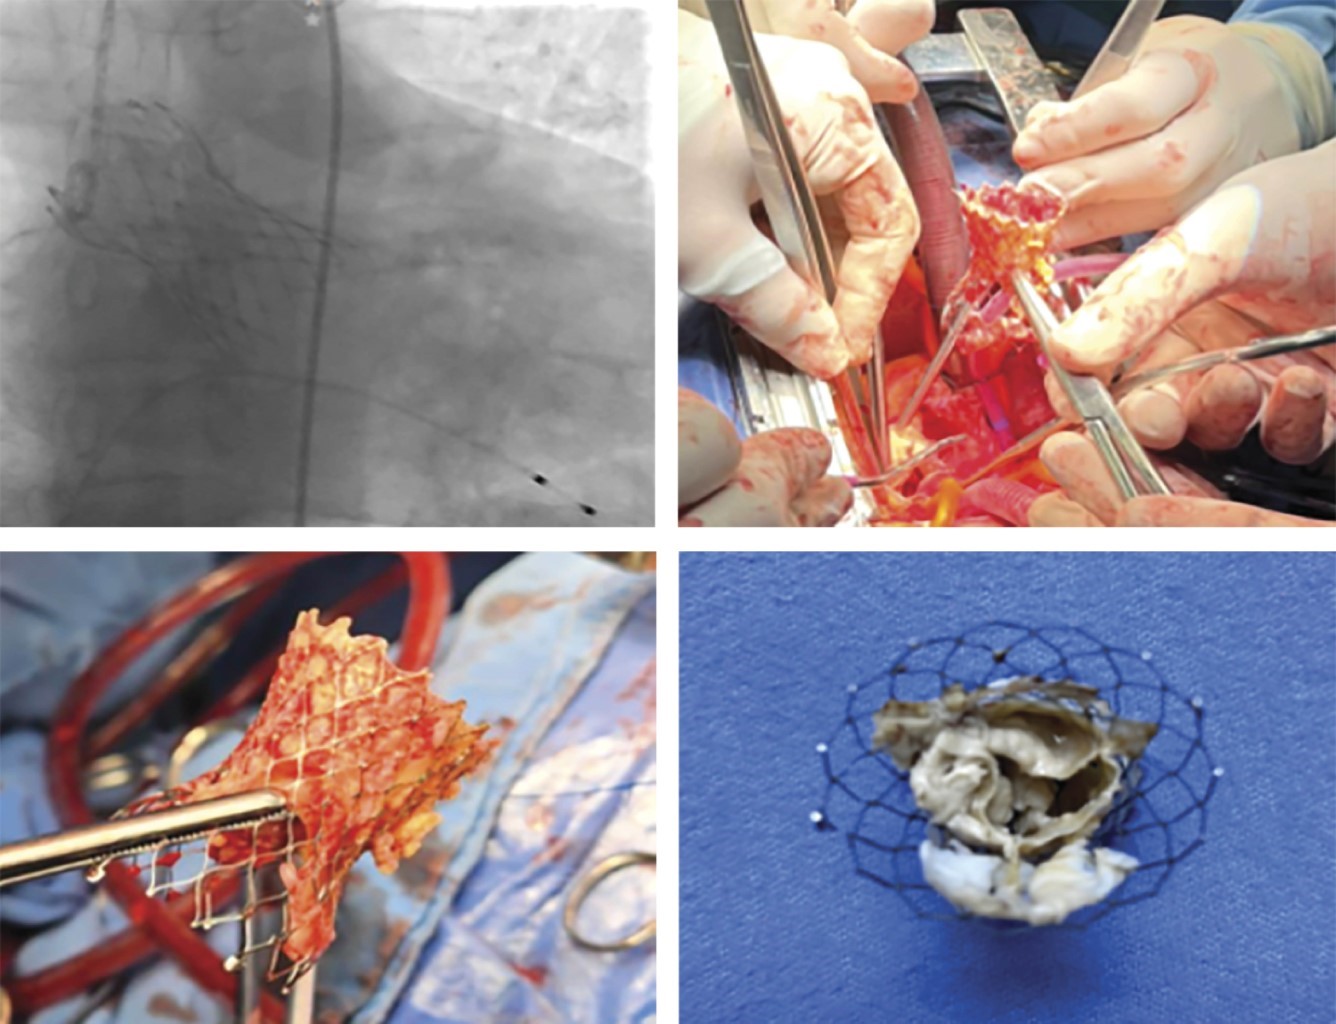

Cirugía en endocarditis infecciosa postreemplazo valvular aórtico transcatéter en dos casos de bajo riesgo

La colocación de válvulas aórticas percutáneas ha pasado de ser un procedimiento para pacientes quirúrgicos de alto riesgo a un procedimiento aceptado en 2019 por la FDA para pacientes de riesgo medio y bajo a nivel mundial. La mayoría de las endocarditis posteriores a TAVI se presentan antes del primer año del procedimiento. Su incidencia es de 0.5 a 2%. Presentamos dos casos de endocarditis infecciosa temprana postreemplazo valvular aórtico transcatéter en dos casos de bajo riesgo quirúrgico.

Figura 1

Figura 2